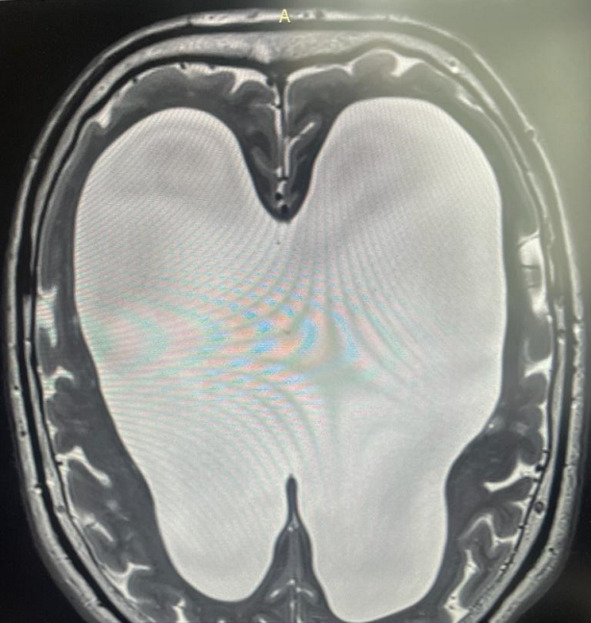

Помимо всего этого, у мозга есть еще одна потрясающая способность – способность сжиматься без какой-либо травмы вещества мозга, если в голове постепенно уменьшается полезный объем. На фото вы видите МРТ человека с нормотензивной гидроцефалией (стр.7), а рядом обычное МРТ (стр.6).

При нормотензивной гидроцефалии объем желудочков мозга увеличивается постепенно. Вы видите, насколько мало места в черепе осталось непосредственно для головного мозга, примерно в два раза меньше нормального объема. И вот этот человек с такими проблемами в голове ходил на работу, начал отмечать замедленность мышления, снижения скорости обработки информации, поэтому обратился к неврологу. Нейрохирурги выполнили ему операцию, после которой желудочки мозга стали нормального размера. И он вновь стал думать так же быстро и великолепно запоминать информацию. И за несколько месяцев сжатия в его мозге не погибли клетки, там не возникло участков некроза, видимых на МРТ. Представьте, если бы мы сдавили мышцы бедра или предплечья. Уже через несколько часов был бы некроз мышц, а здесь несколько месяцев – и без последствий. Таким образом, компенсаторная способность к уменьшению объема у мозга совершенно поражает воображение.